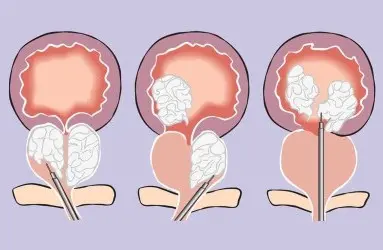

Tedaviler

Üroloji Uzmanı